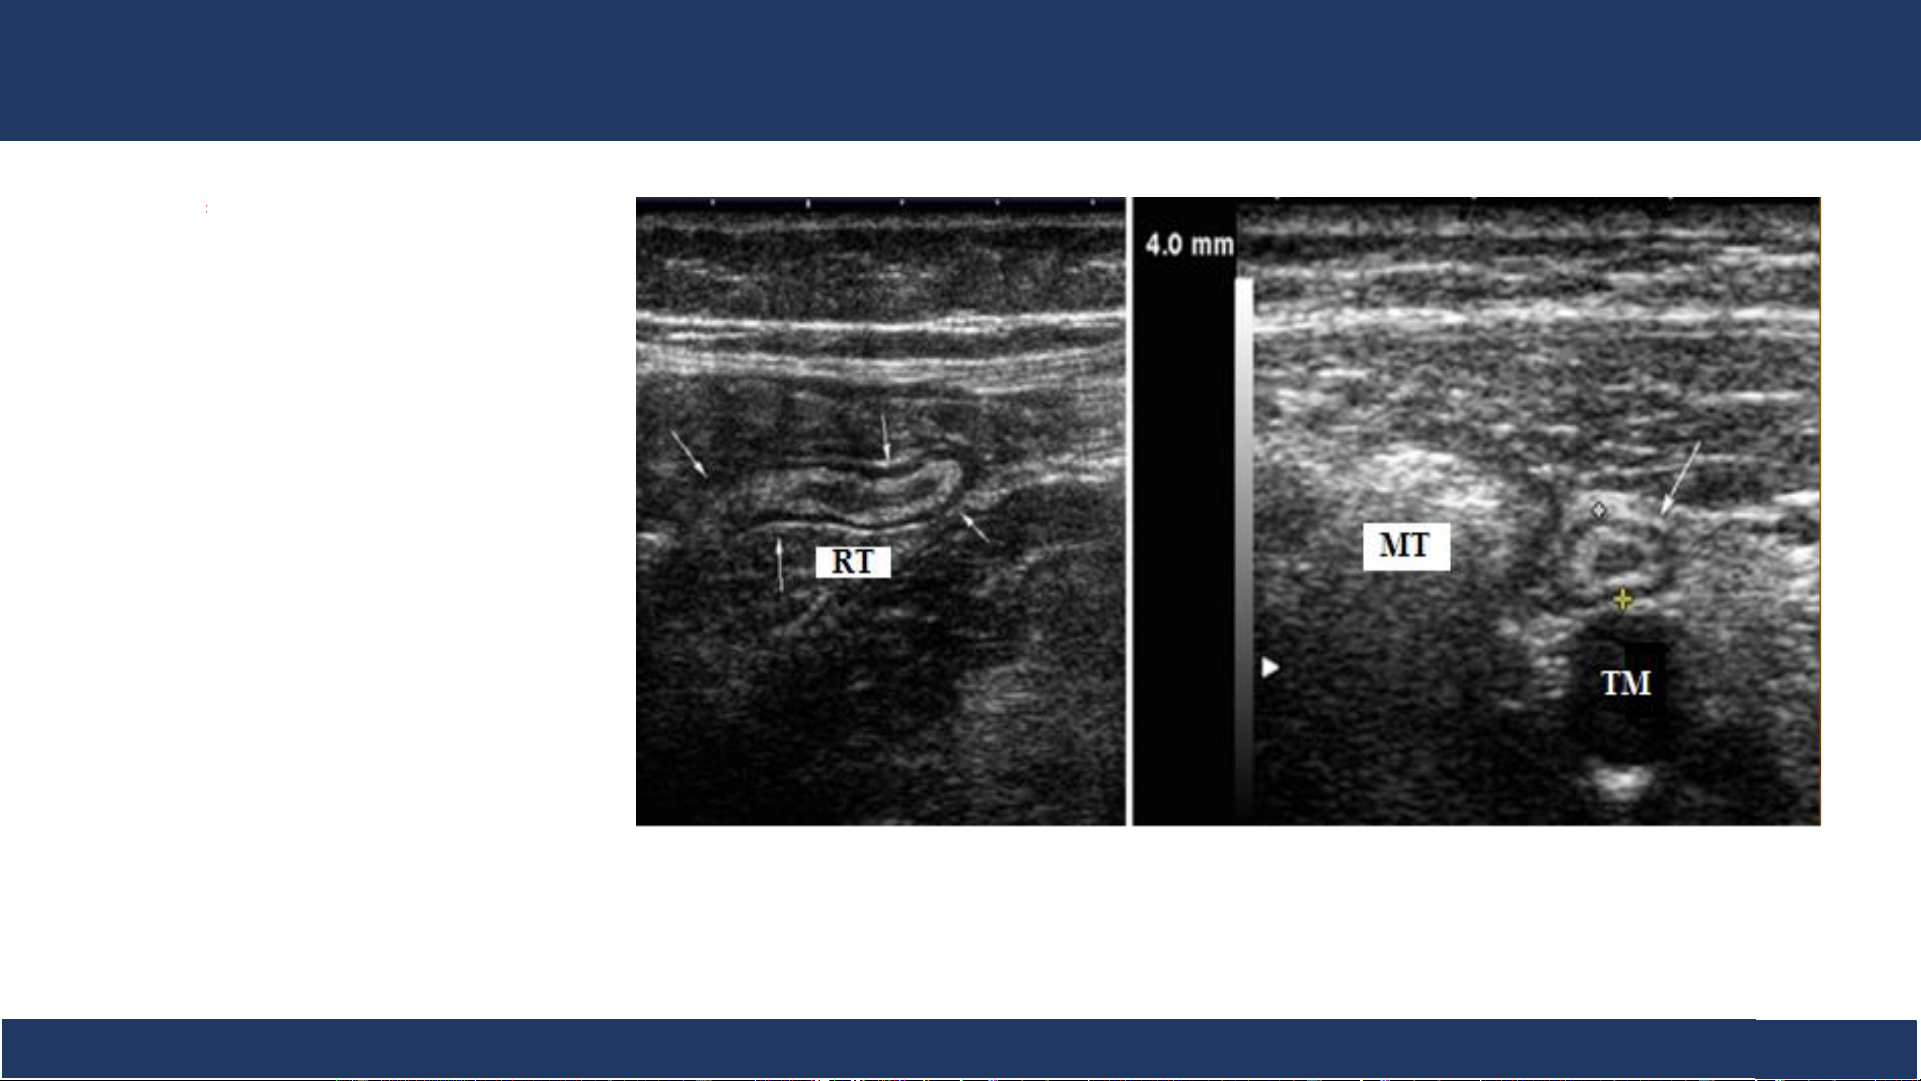

hình ảnh, ĐHYD TPHCM 16 SA: ruột thừa . Cấu trúc ống tiêu hóa xuất phát từ manh tràng, có đầu tận, không nhu động. Cắt dọc Cắt ngang RT: ruột thừa (mũi tên). MT: manh tràng TM: tĩnh mạch chậu Bệnh v B iệ ộ môn n Nh Chẩ i Đồng n đoán 1